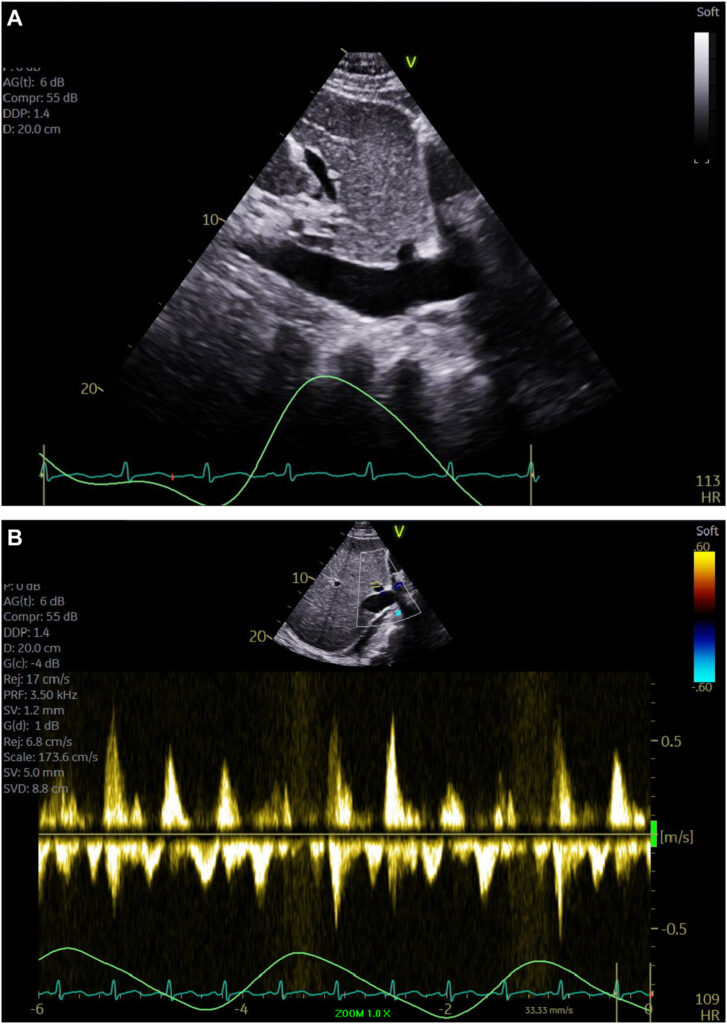

Um ecocardiograma foi novamente realizado e um importante derrame pericárdico foi documentado, contudo com aspecto multiloculado resultando em compressão de todas as 4 câmaras cardíacas.

Havia colapso diastólico da região apical e da parede lateral do ventrículo esquerdo, além do colapso do VD.

Também foi observado um espessamento do pericárdio (4 mm) com tethering da parede livre do VD e da parede lateral do VE caracterizado pela ausência da movimentação tipo deslizamento entre os folhetos parietal e visceral do pericárdio.

Havia ainda uma variação importante, durante o ciclo respiratório, nas velocidades dos fluxos tricúspide (aumento de 44% durante a inspiração) e mitral (redução de 25% durante a inspiração).

A VTI, avaliada na janela apical 3C, foi de 8.8 cm para 6.2 cm, conferindo uma redução de 30% durante a inspiração. Tal achado é consistente com a variação inspiratória do volume sistólico ejetado. A veia cava inferior estava pletórica (2.3 cm) com variabilidade inspiratória de 22%. Ainda, havia fluxo reverso na veia hepática durante a expiração.